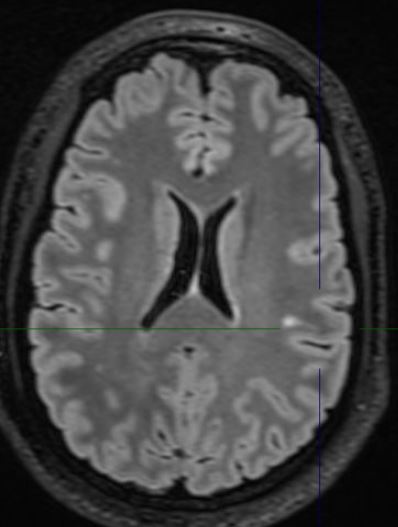

The MRI demonstrates a juxta-cortical, linear lesion in the white matter of the left post central gyrus extending medially to above the insular cortex. There is no mass effect and no enhancement. The nature of the lesion is unclear and does not relate to any of his symptomatology. His loss of consciousness almost certainly was related to a very large binge on alcohol, with very high blood alcohol levels. There is no history of any right facial or any other sensory symptomatology, nor of any episodic or persistent language dysfunction. There is no history of previous cranial trauma. His perinatal and developmental history is unremarkable.

In addition to the above lesion there are a few other punctate white matter lesions. It is presumed that these are old and have been discovered coincidentally as they do not relate to any past or recent symptomatology and are therefore "asymptomatic". I discussed the case with experienced neuroradiologist who reports that the lesions appear "innocuous".  The case also makes the point that diagnostic tests may result in a lot of harm; in this instance the patient was effectively "medically deported" within 24 hours of the scan having been done in a highly developed country. If the EEG is misinterpreted, the patient's problems will only be compounded. His EEG was normal for 72 hours; the rationale for performing it for this duration will be discussed at a later stage